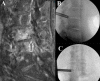

Results: Collectively, 19 cases described endoscopic spine surgery for spinal oncologic care. Endoscopic spine surgery has been employed for the care of patients with spinal tumors under the following 4 circumstances: (1) to obtain a reliable tissue diagnosis; (2) to serve as an adjunct during traditional open surgery; (3) to achieve targeted debulking; or (4) to perform definitive resection. These cases employing endoscopic techniques highlight the versatility of this approach and its utility when applied to the right patient and with an experienced surgeon.